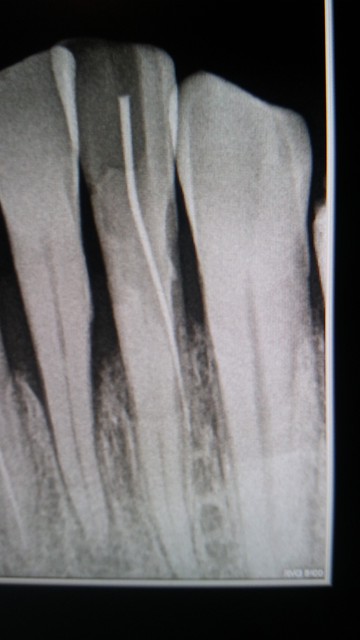

A la suite d’une dévitalisation dentaires, je me retrouve avec trois dents de devant perforées.

Le dentiste me l’a caché et essayant tout de même de me couronner ces dents là. Suite au douleurs j’ai été voir un autre dentiste et a la radio il a vu que mes 3 dents sont perforées.

On me dit qu’une extraction d’urgence est nécessaire, je suis perdue je ne sais que faire.